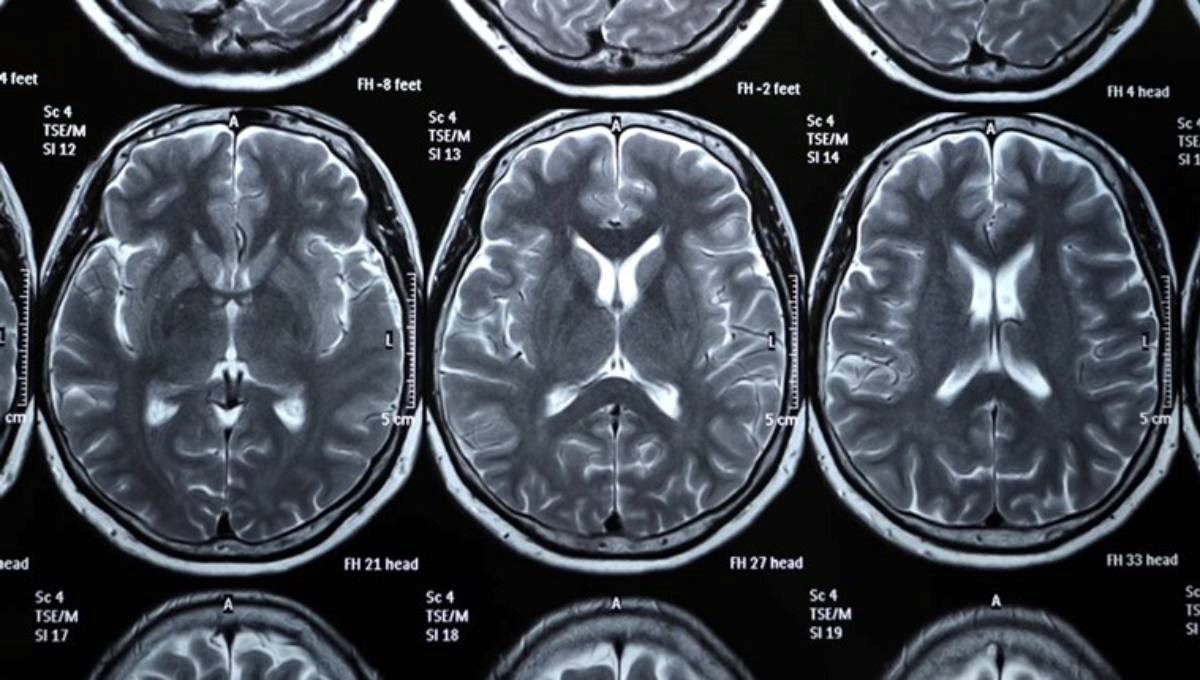

KAKO vrijeme prolazi, tako se ljudi mijenjaju. Izgleda da mlađe generacije nisu samo dobile na centimetrima u visini - već i u volumenu mozga.